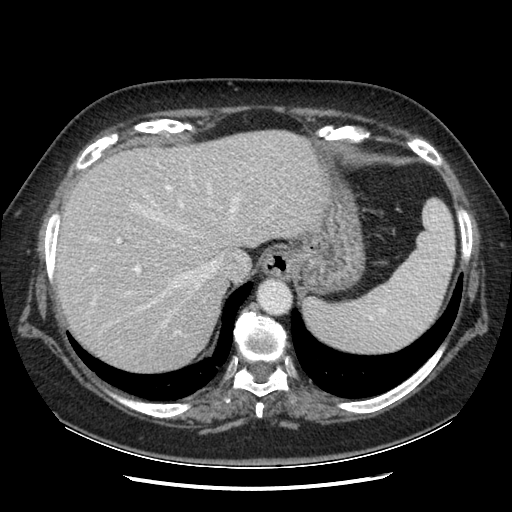

Generated VENOUS CT scan (A→B translation)

Full window (WL 1023.5, WW 4095 β†’ Low βˆ’1024, High +3071)

Actual HU range: [-1024.0, 695.6]